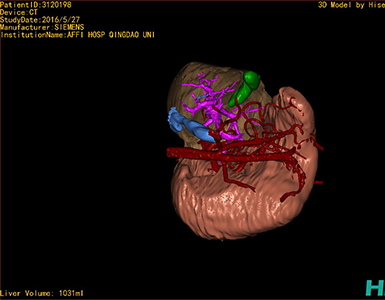

CT结果输入海信CAS系统后行3D重建及手术规划后,于2016-6-28全麻下行“劈离式肝移植(左半肝,背驮式)”手术治疗。

将0.625mm双源薄层CT资料的静脉期和动脉期Dicom格式文件导入海信CAS系统。

通过调节窗宽窗位调整CT序号,对肝实质,胆囊,下腔静脉,肝动脉、门静脉及肝静脉等进行三维重建,明确血管走行;系统自动计算肝脏体积。

模拟手术操作,肝脏体积为1052ml,通过比对11-12岁正常肝脏体积为1116.86±158.78ml,建议进行肝移植手术。

术前三维重建:

重建图片